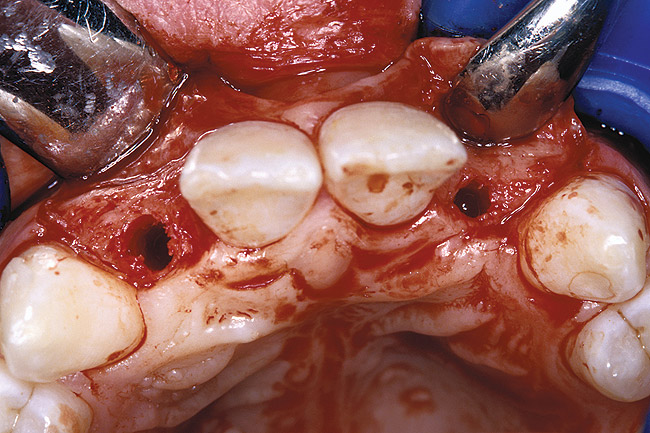

Before the day of surgery, the patient was seen by the orthodontist for the removal of the orthodontic brackets. The patient still was not pleased with the position of the two centrals, and it was determined that this would be addressed after implant placement (Figure 26). The anatomical variations of the crestal tissue and lack of interdental papilla can be appreciated in the close-up views of the right and left sites (Figure 27 and Figure 28). There were no surprises on the day of surgery as all of the decisions were made during the planning phase, before the scalpel ever touched the patient. The occlusal view of the CT 3D model revealed the wider alveolar ridge on the right side and thinner crest on the left side (Figure 29). This was confirmed when the full-thickness mucoperiosteal flaps were elevated, and the underlying bone revealed (Figure 30). The tooth-borne templates were designed to facilitate the drills and drilling sequence specific to the diameters of the predetermined implants (Figure 31). Each template contained an embedded 5-mm long stainless steel tube, which was approximately 0.2-mm wider than each drill (just wide enough to allow for the drills to rotate freely). Once positioned over the natural teeth, the template was secure and offered precision accuracy in transferring the implant locations from the original software-designed plan, allowing the potential for internal and external irrigation (Figure 32).

Figure 30  VIRTUAL PLANNING AND SURGERY The information gained from the 3D model was confirmed when the flaps were elevated.

Figure 30